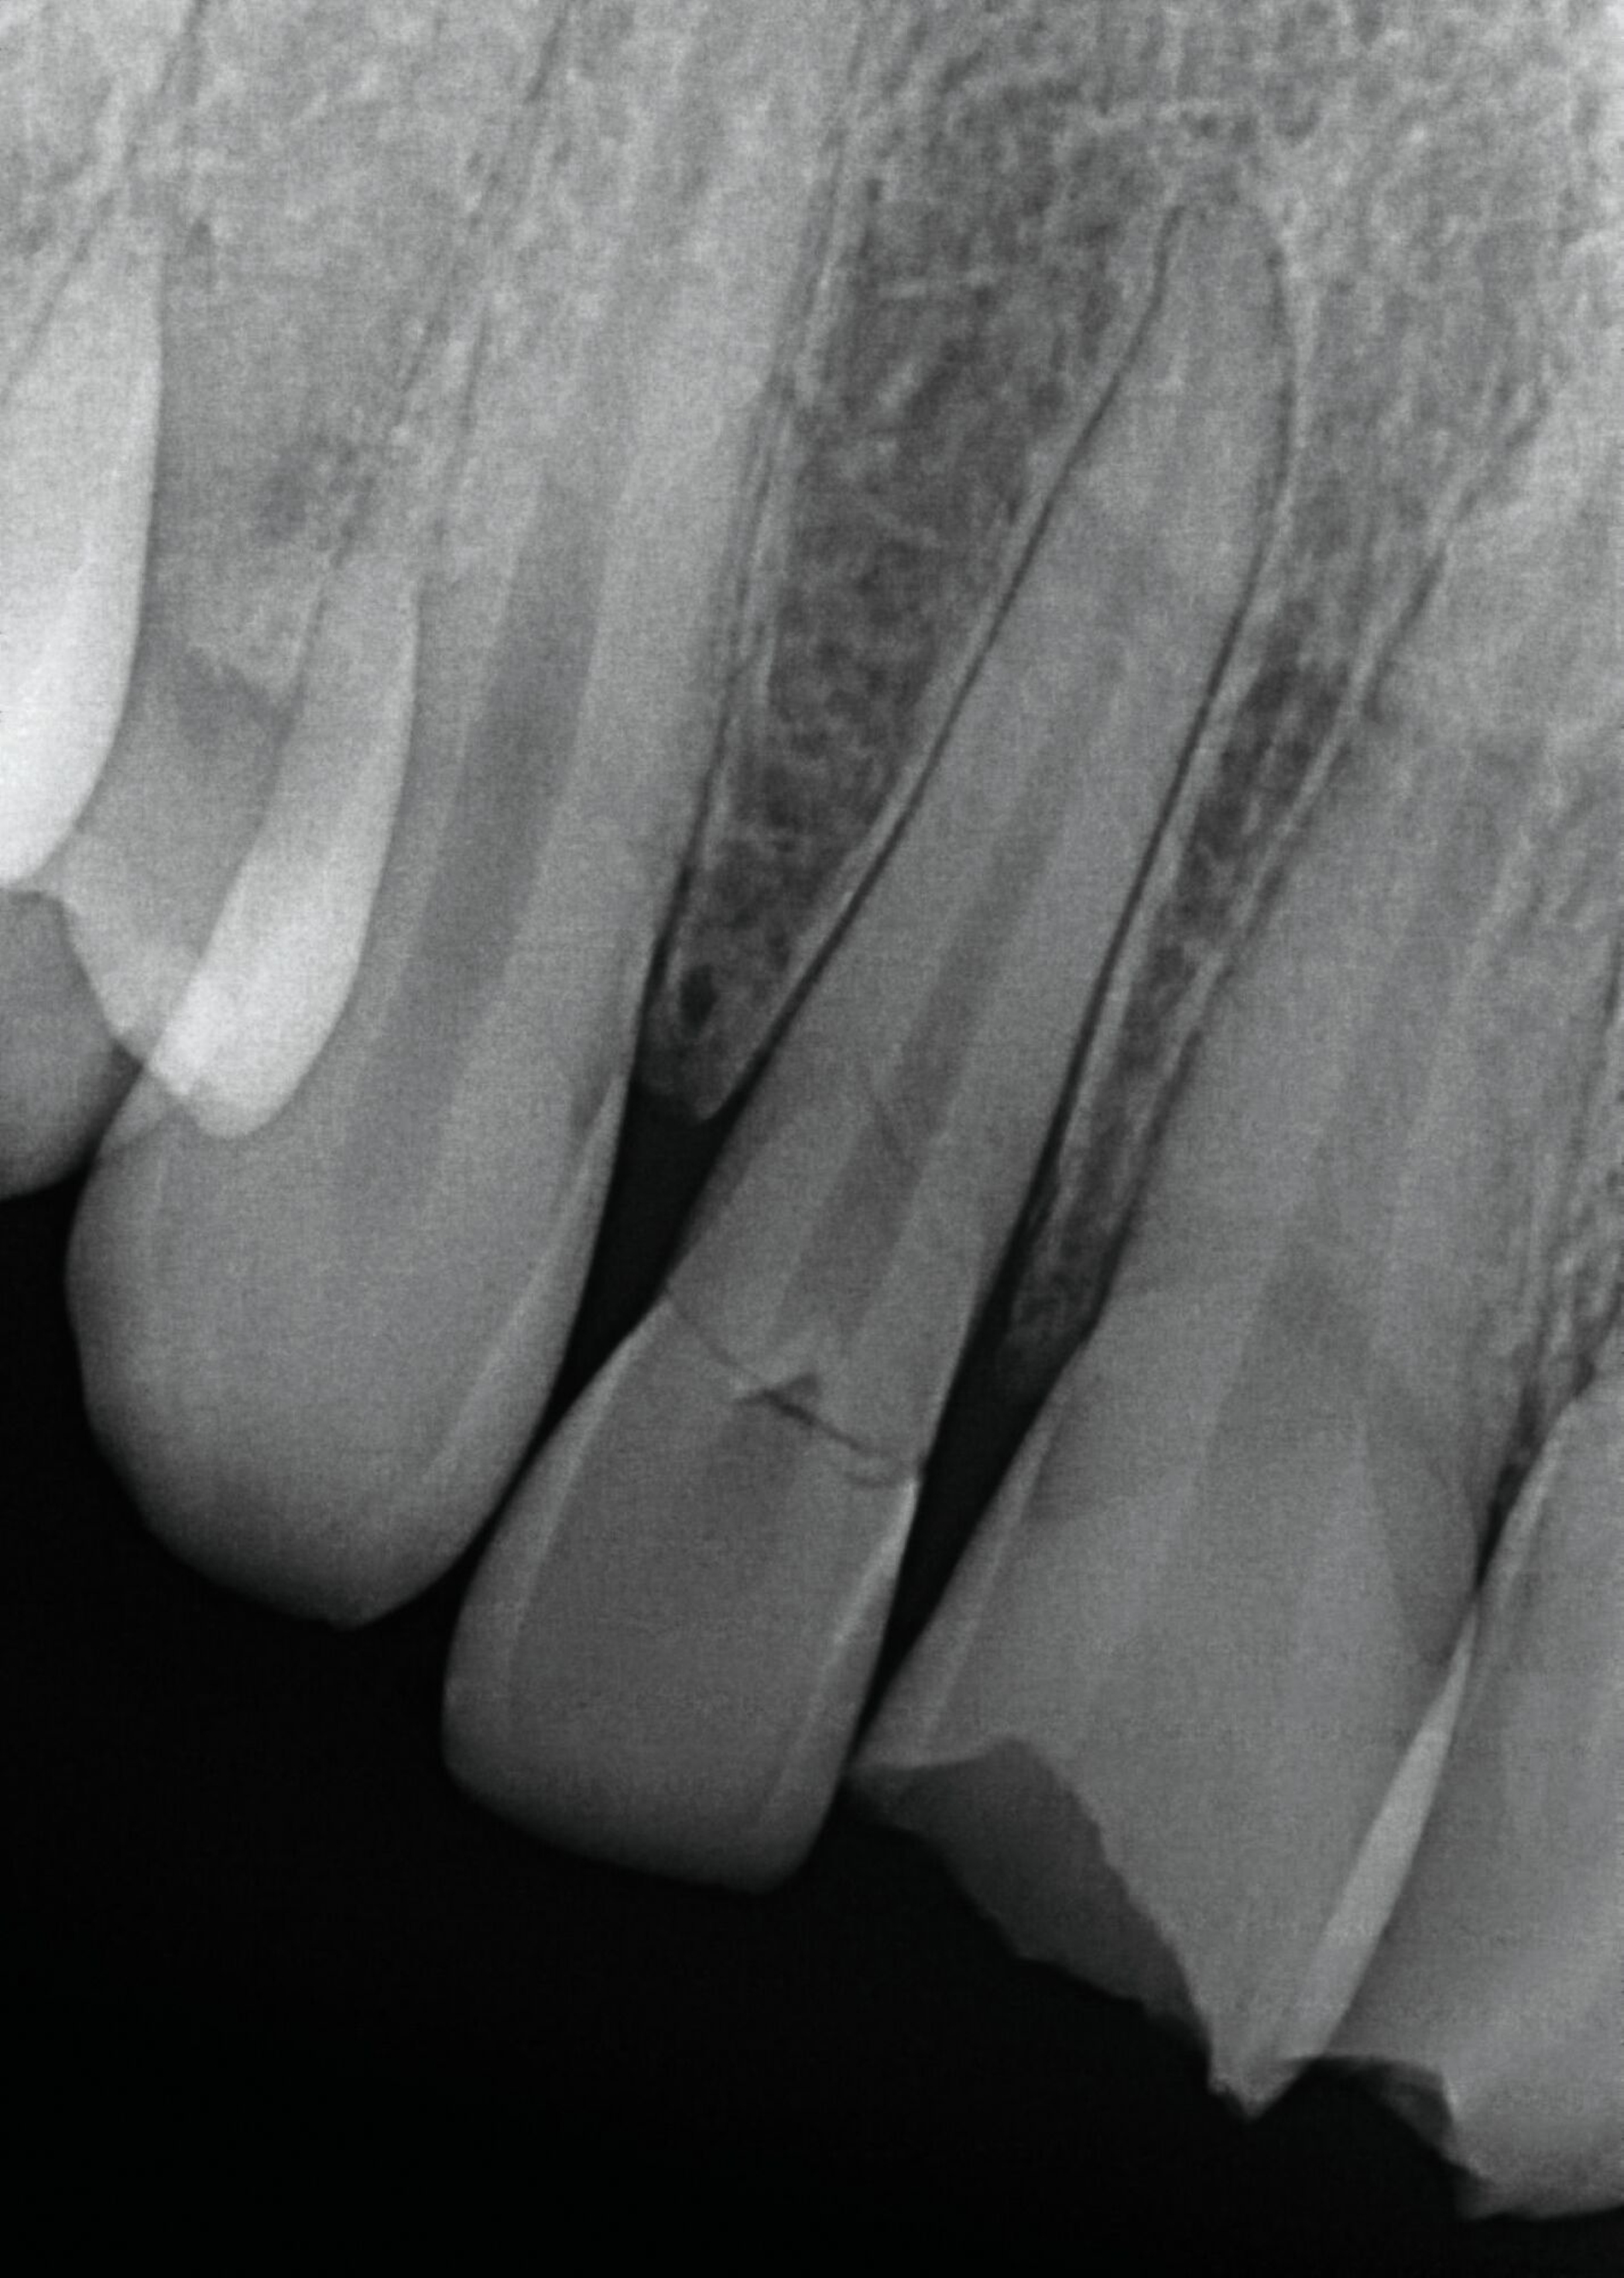

Die adhäsive Wiederbefestigung mitgebrachter Kronenfragmente bietet sich als einfache und konservative Methode zur Wiederherstellung von Funktion und Ästhetik an (Abbildung 1). Wenn das Fragment nach dem Unfall unter feuchten Bedingungen gelagert wurde, wird die Wiederbefestigung idealerweise sofort während der Notfallbehandlung durchgeführt. Wurde das Fragment jedoch durch eine längere Trockenlagerung dehydriert, sind sowohl das ästhetische Ergebnis als auch die Komposithaftung kompromittiert. In solchen Fällen wird eine Lagerung in physiologischer Kochsalzlösung oder in Wasser für einen Tag empfohlen, um eine Rehydrierung des Fragments zu ermöglichen [Farik et al., 1999], während das Dentin in der Zwischenzeit mit einem leicht entfernbaren temporären Material bedeckt ist (zum Beispiel Kalziumhydroxid-Zement). Die Rehydrierungszeit kann durch eine feuchte Lagerung des Fragments in einem sauberen Drucktopf auf 30 bis 60 Minuten verkürzt werden.